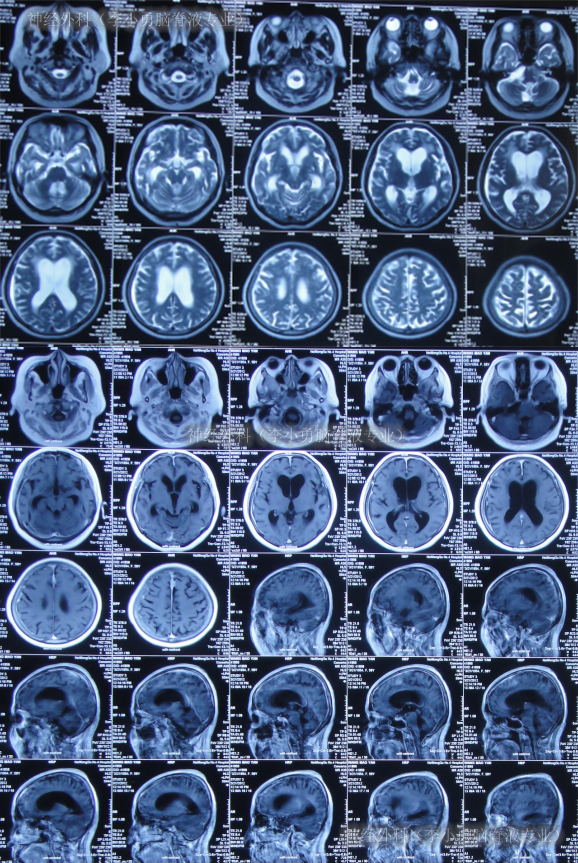

第2家医院出院1月余即2012年2月7日,夜里起夜突然又重复发作以前的症状(恶心呕吐、头昏),且比前2次发作严重,2012年2月8日住入第3家医院:呼和浩特市某三甲医院的神经外科治疗,入院查头颅CT(图-2)和MRI(图-3);脊髓核磁(图-4);肺部CT(图-5)及多次腰椎穿刺脑脊液化验检查(糖低、蛋白高),诊断为:结核性脑膜炎,脑积水。

图-5:2012年2月9日肺部CT